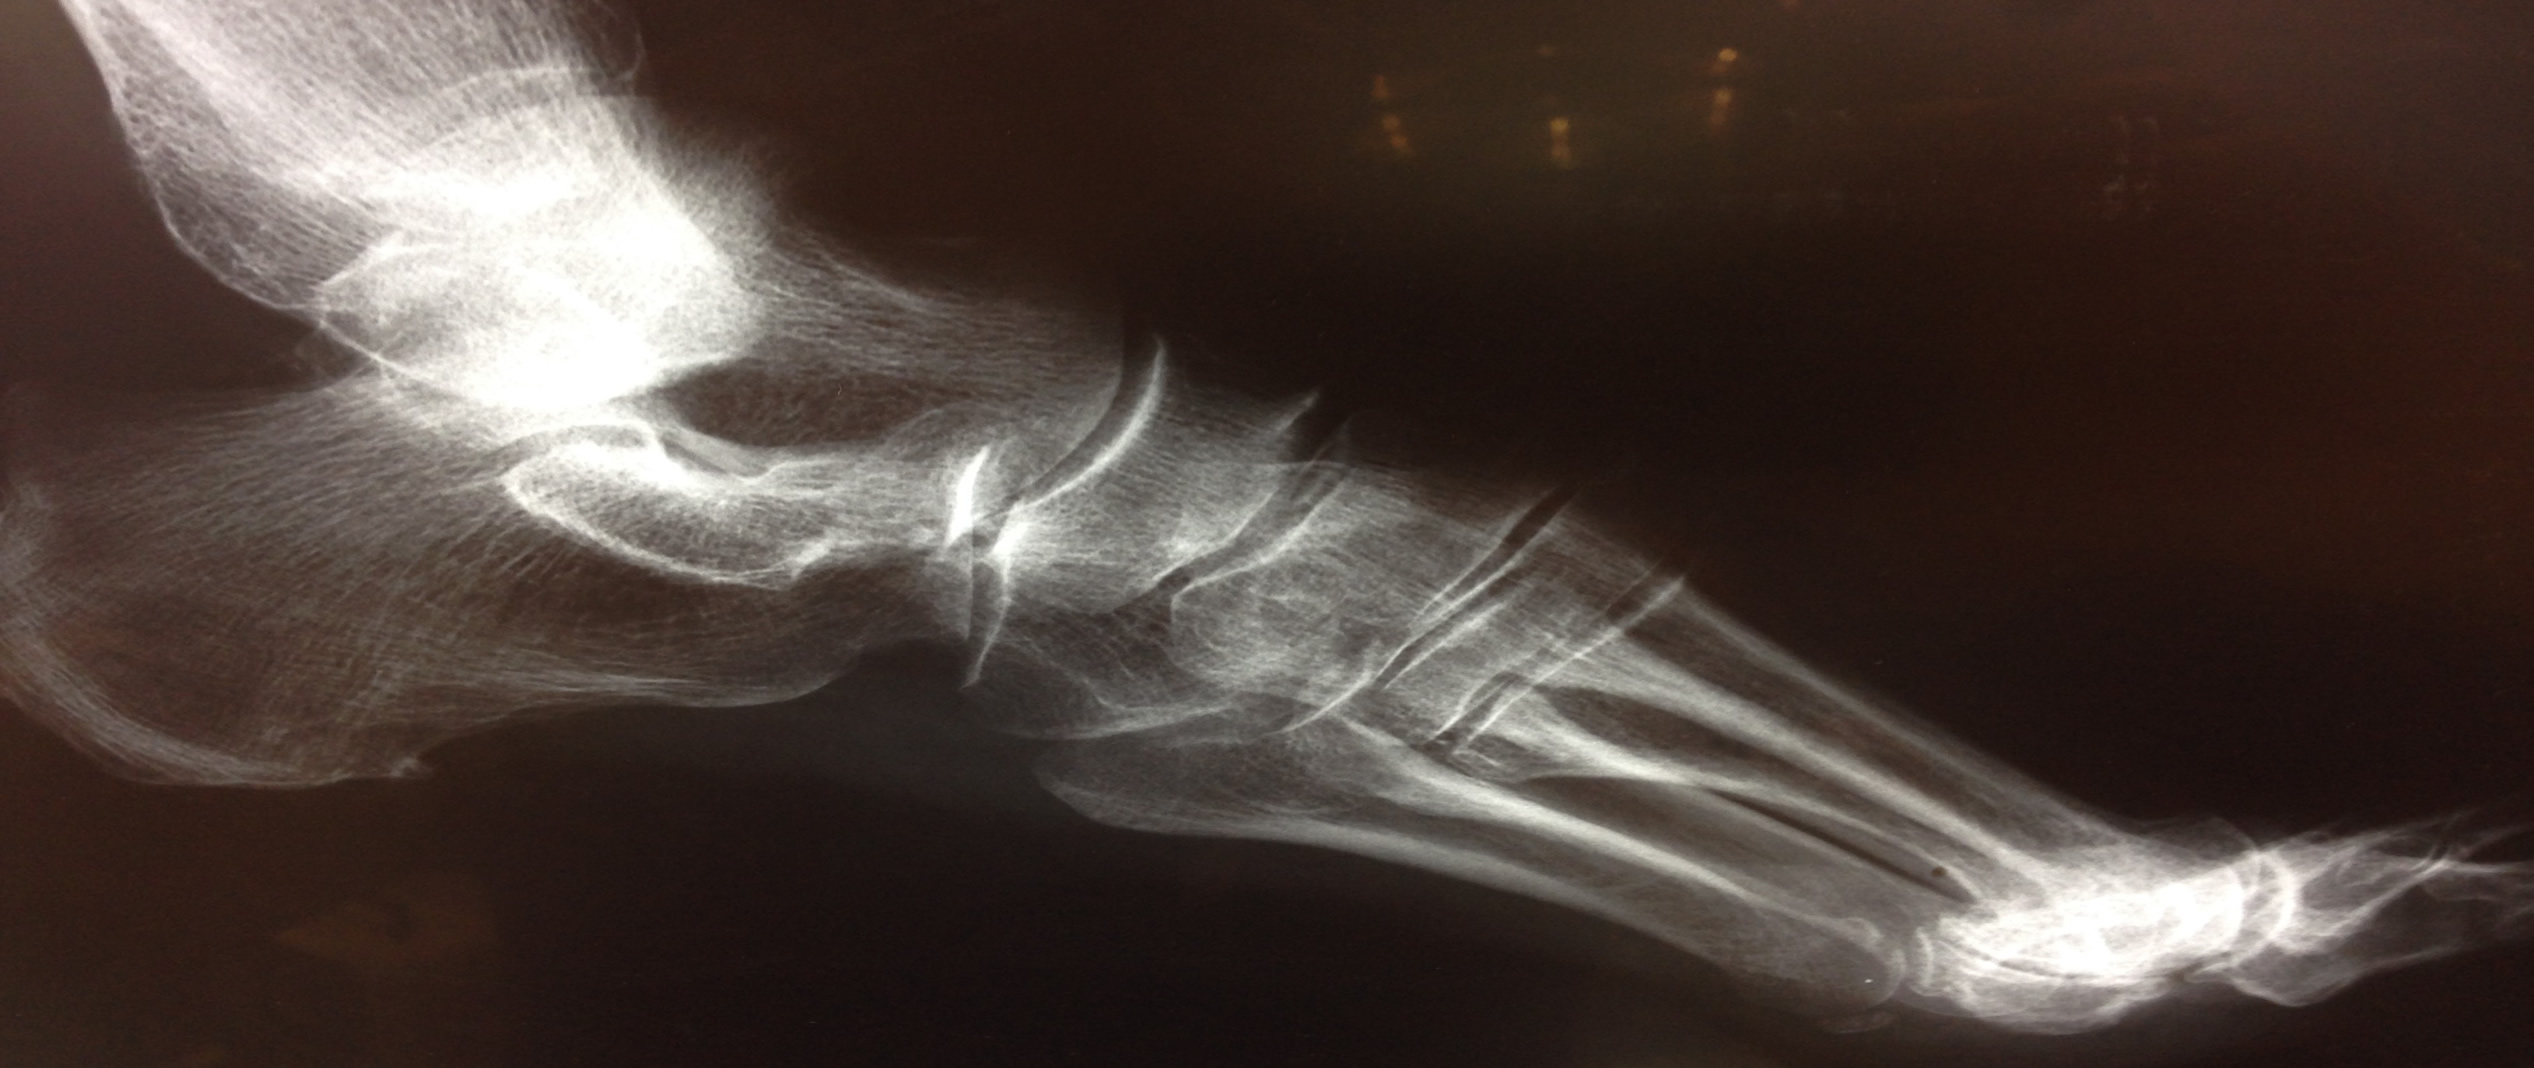

"Avevo il piede destro con l'osso dell'alluce che sporgeva, un forte dolore a camminare e a calzare le scarpe. Dopo una visita specialista con il Dr. Luca Putzulu è stato subito riscontrato che soffrivo di alluce valgo e, dopo aver fissato una data per l'intervento chirurgico, dopo 15 giorni il mio alluce valgo è stato curato grazie all'intervento del Dr. Luca Putzulu e del suo staff."

"Avevo un forte gonfiore sotto la pianta del piede e un dolore acuto che si diramava in tutto il piede, con difficoltà a calzare le scarpe. Dopo la visita il Dr. Luca Putzulu ha riscontrato che soffrivo di una patologia chiamata morbo di Ledderhose. Dopo varie analisi sono stato operato e in poco tempo ho risolto il mio problema."